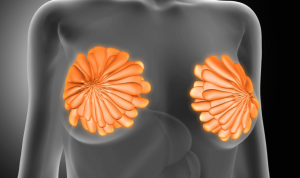

El aneurisma aórtico se caracteriza por una dilatación patológica en puntos específicos de predilección del vaso y puede acabar en una ruptura vascular potencialmente mortal. Las zonas en las que se forman los aneurismas vasculares suelen ser las más afectadas por estos incidentes, incluso en personas sanas, como demuestra un estudio realizado por investigadores médicos de Bochum y Bonn (Alemania). “Queríamos entender por qué siempre son estos lugares los más afectados, también qué los distingue de los demás”, señaló la prof. Daniela Wenzel, jefa del Departamento de Fisiología de Sistemas de la Universidad del Ruhr en Bochum.

Para obtener respuesta a sus planteamientos, utilizaron un método para examinar específicamente el endotelio de la aorta: la capa más interna del vaso sanguíneo. “Sabemos por otras enfermedades vasculares como la arteriosclerosis, que se producen cambios en esta capa más interna mucho antes de que aparezcan los síntomas“, de acuerdo con esta investigadora.

Elasticidad del endotelio

Estos expertos pudieron constatar que cuanto menos elástico es el endotelio, más perjudicial es para la salud vascular. Así, demostraron que el endotelio era más rígido en los lugares donde se forman con frecuencia aneurismas que en las áreas de control.